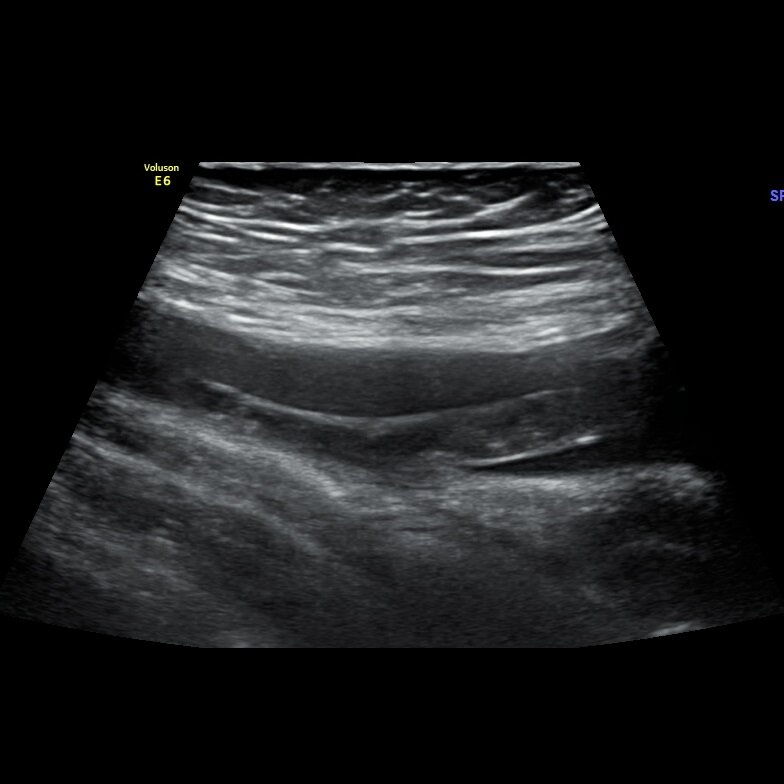

Тромбоз бедренной вены

🏥Пациент лечится по онкологическому заболеванию, проходит плановое УЗИ перед очередным курсом терапии. Боли в ноге уже почти месяц, отек не выражен. В бедренной вене эхогенный тромб, фиксация в бедренной вене, подвижный конец тянется на 7см, выше гбв но ниже сфс на 1.5 см.

🗒️Хронический не окклюзивный тромбоз, фиксированный тромб с подвижным концом. Пациент направлен к хирургам.